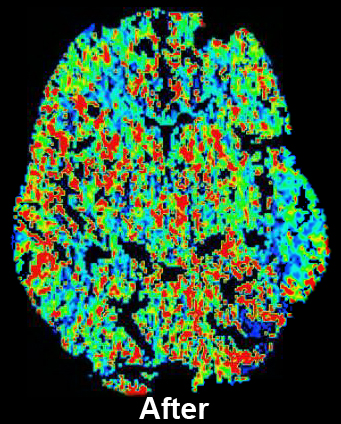

CT Perfusion with Diamox scan for Radiology- After

CT Perfusion with Diamox scan for Radiology- Before

How it works: CT perfusion with acetazolamide (Diamox) consists of a baseline CT perfusion scan of a portion of the brain, followed by injection of acetazolamide (a vasodilatory agent), and then a post acetazolamide CT perfusion scan of the same area. Normally, if blood flow to the brain is decreased, the vessels for that area will expand to maintain adequate oxygen flow, up to a maximum limit. The extent to which this can occur beyond baseline is the cerebrovascular reserve. CT Perfusion with acetazolamide allows assessment of the cerebrovascular reserve.

Equipment: Perfusion studies are usually performed on a Philips 64 or 256 channel CT scanner. OHSU is an ACR accredited CT facility.

Benefits: The study is used to evaluate cerebrovascular reserve, which can help determine the risk of future stroke. The study is often used to help determine which patients might benefit from interventions designed to increase blood flow beyond a very narrow or occluded vessel.

Exam Preparation: Exam preparation is the same as for a CT perfusion study, with additional screening for any potential contraindications to acetazolamide. Additional lab work of sodium and potassium levels are necessary if not performed within two weeks. Potential contraindications to acetazolamide include: Sulfa/sulonamides, severe renal dysfunction, cirrhosis/severe liver disease, adrenocortical insufficiency, hyponatremia, and hypokalemia. A nurse or technologist will interview you for contraindications, and an IV will be placed. Usually labs will be needed prior to the study.

What to Expect: A baseline perfusion scan is performed, followed by injection of acetazolamide over several minutes. It takes about 15 minutes for acetazolamide to have its maximal effect. A post acetazolimde perfusion scan is performed about 15 minutes after injection. Because of this time between scans and the additional time necessary for screening and possible lab work, the amount of time spent in the department will likely be between 1 and 2 hours.

Severe reactions to a single dose of acetazolamide are rare; however, more common reactions that are usually self limited can include brief numbness around the mouth, paresthesias, malaise, and headache.

Adverse reactions to contrast materials are uncommon, but can range from mild to severe. Severe reactions very uncommon. Further information about the risks and benefits of x-rays and contrast material can be found here.

Content by Dr. Louis P. Riccelli